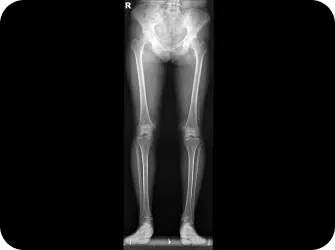

전신 엑스레이 검사

다리길이 엑스레이 검사

Before & After

해당 사진은 수정없는 실제 치료사진입니다.

환자의 치료결과는 환자의 상태, 치료방법 등에 따라 차이가 발생할 수 있습니다.